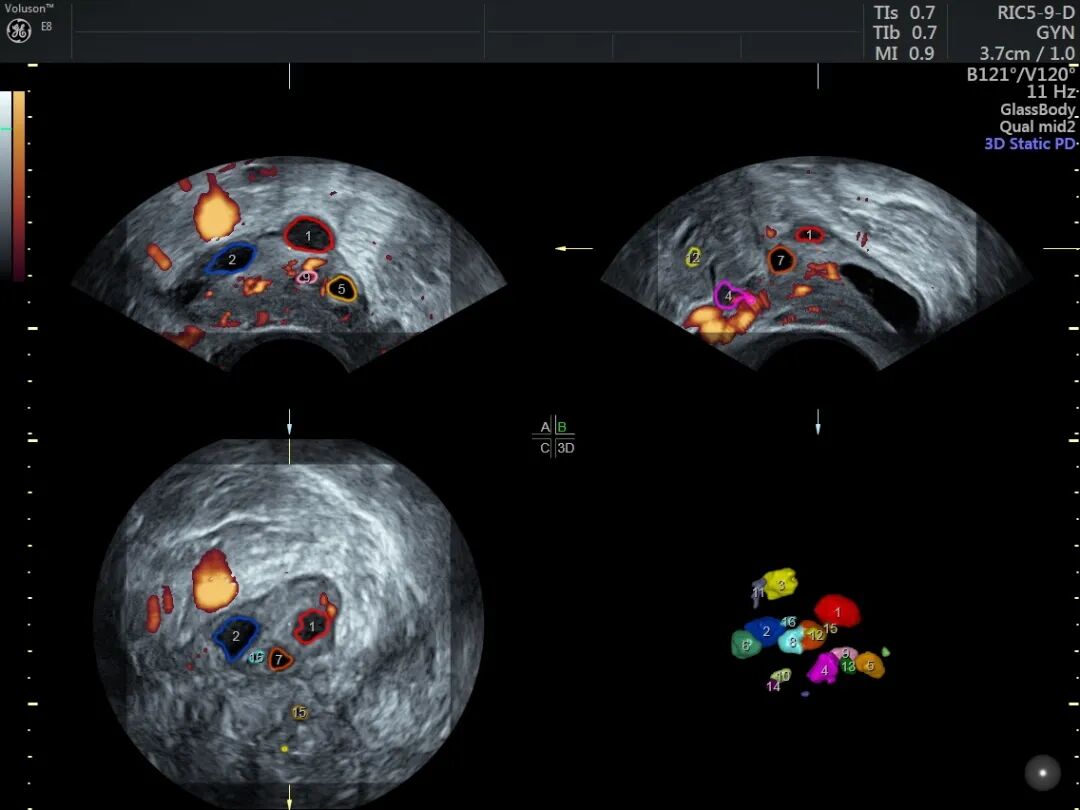

卵巢储备功能超声评估

卵巢储备功能指卵巢产生卵子数量和质量的潜能,间接反映卵巢的功能。最常用的超声指标有基础窦卵泡数(AFC)、卵巢体积、卵巢基质血流。

窦卵泡计数